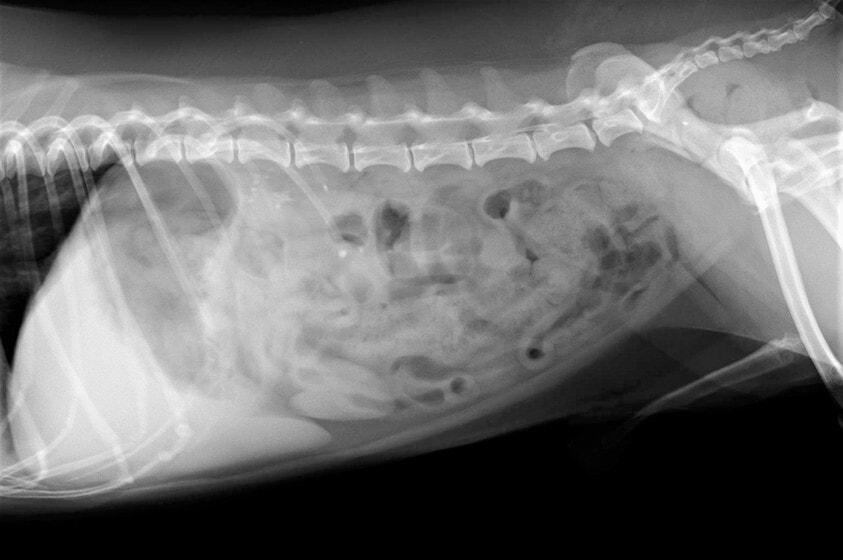

術後レントゲン

腹部臓器が腹腔内に戻り、腹部と胸部の境界および心臓や肺の陰影が明瞭に見えるようになりました。